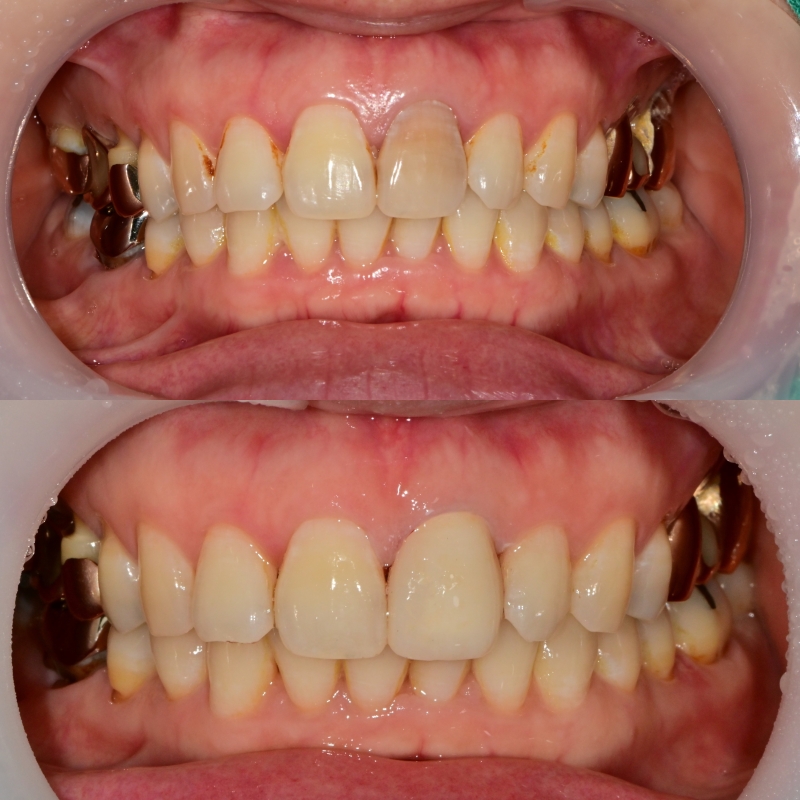

치아 색 맞추는 단계

어둡게 비추는 부분을 커버하기 위해

여러 색을 대조해 보고 수정을 하는 과정이 필요했습니다.

앞니 심미보철을 제작할 경우에는

하나의 치아를 주변 기존 치아에 맞춰서 제작하는 것은

주변 조건을 다 충족시키기 어렵고 분명 한계는 존재합니다.

다행히 주변 치아들의 캐릭터가 평범했기 때문에

좋은 결과물이 나올 수 있었던 것 같습니다.

전후 사진 비교

이렇게 앞니의 보철치료는

기능적 뿐만 아니라 심미적인 요인도

작용하기 때문에 치료 결정에는

여러 요인이 작용하는 부분입니다.